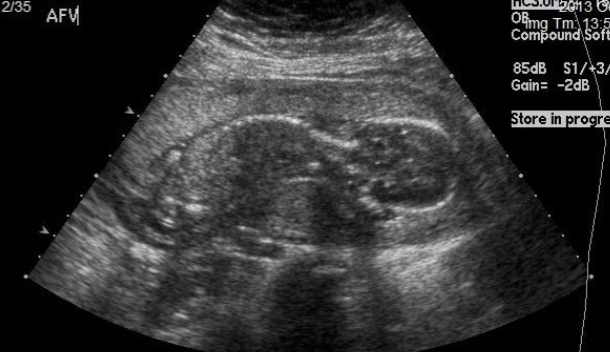

PROM U/S findings:

oligohydramnios

anhydramnios